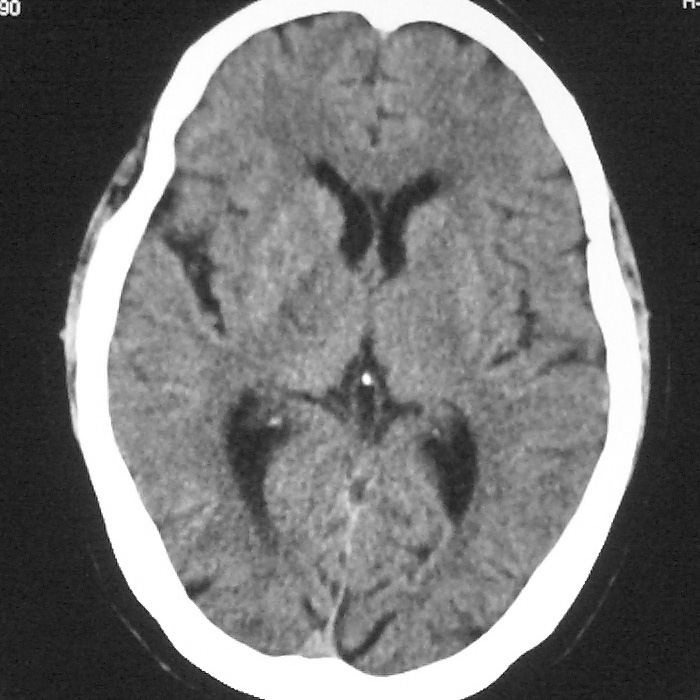

f,70y,口角歪斜、流涎、吐词不清三天

症状这么明显的话一般不会是单纯面神经麻痹引起的,最好做个mri,如果确实没有问题的话才能考虑面神经麻痹,毕竟这两种病的治疗和预后不一样,这个病人还有脑白质疏松。

双侧多发腔梗

1、右侧基底,左侧半卵圆中心腔梗。2脑萎缩。

皮层下动脉硬化性脑病。

左侧半卵圆中心,右侧基底节腔梗。再加个脑萎缩吧

双侧多发腔梗 脑萎缩